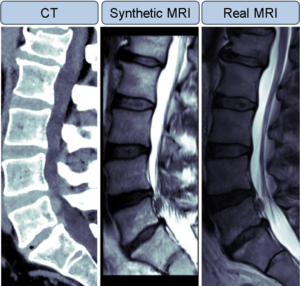

Prof Peter MacMahon was also awarded a Health Innovation Hub Ireland (HIHI) Clinical Innovation Award 2024 for the project “SuperCT Spine: Enhancing Lumbar Spine CT with AI for Early Detection of Cauda Equina Syndrome”